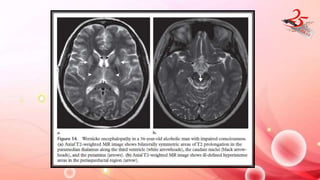

WERNICKE ENCEPHALOPATHY

• CAUSE: Vit B1 def , Chronic alcoholics , GI or hemat neoplasm ,

chronic dialysis , prolonged TPN without vit supplementation.

• CLINICAL FEATURES : altered consciousness, ocular dysfunction, and

ataxia

IMAGING FINDINGS:

• MRI : Symmetric T2 hyperintensity in medial thalamus ,

periaqueductal area , mammillary body and tectal plate.

• Petechial hemorrhage , diffusion restriction and contrast

enhancement of affected areas

WERNICKE ENCEPHALOPATHY • CAUSE:Vit B1 def , Chronic alcoholics , GI or hemat neoplasm , chronic dialysis , prolonged TPN without vit supplementation. • CLINICAL FEATURES : altered consciousness, ocular dysfunction, and ataxia IMAGING FINDINGS: • MRI : Symmetric T2 hyperintensity in medial thalamus , periaqueductal area , mammillary body and tectal plate. • Petechial hemorrhage , diffusion restriction and contrast enhancement of affected areas